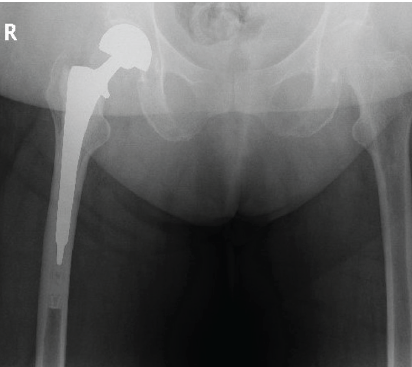

The patient underwent right hip hemiarthroplasty (Fig. 2). A standard anterolateral approach was utilized. The femoral stem was cemented, a standard neck +3 bipolar head was used, and good intraoperative stability and length were confirmed. Due to a platelet count of 42 and hemoglobin of 8, she was given platelets and packed red blood cells (PRBCs) intraoperatively. She tolerated this surgery well. She was weight bearing as tolerated (WBAT) postoperatively.

Figure 2: Anterior-posterior X-ray depicting right hip hemiarthroplasty.